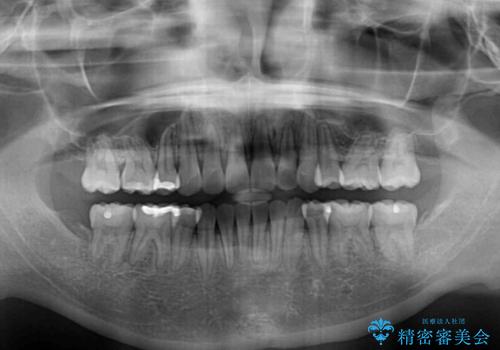

- 上下の出っ歯を気にして来院された患者様です。

口元を積極的に引っ込めるために、上下左右の第一小臼歯を4本抜歯することとしました。

下顎の正中を上顎に合わせる処置が難航し、期間が長引きました。

最終的には上下の正中も合い、横顔の印象が変わるほどスッキリとした口元となりました。